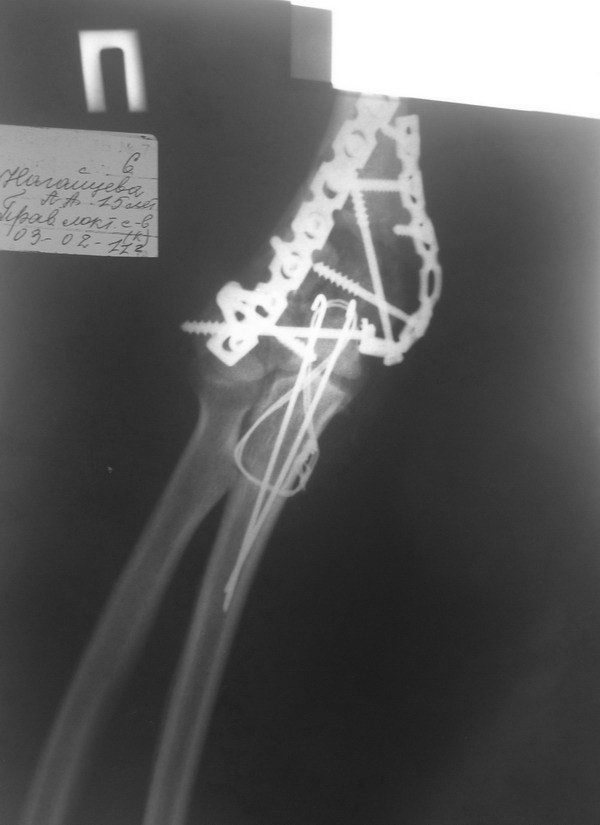

Уважаемые коллеги. Помогите советом определится с тактикой дальнейшего лечения. Пациентка, 16 лет. В 02.2011 - тяжелая сочетанная травма ОДА, груди, живота. В т.ч.открытый многооскольчатый чрезмыщелковй перелом правого плеча и локтевого отростка

Прооперирована на 2 сутки - остеосинтез реконструктивными пластинами плеча и локтевого отростка по типу Weber. В мае 2011 - явления спицевого остеомиелита на фоне слабой консолидации . Спицы удалены. Свищи закрылись. Больная ушла на реабилитацию в поликлинику.

Имя     : 02.2011 800.jpg

Тип     : image/jpg

Размер  : 46154 байтов

Описание: отсутствует

Url     : http://weborto.net:8080/pipermail/ortho/attachments/20120313/c909356e/attachment-0006.jpg